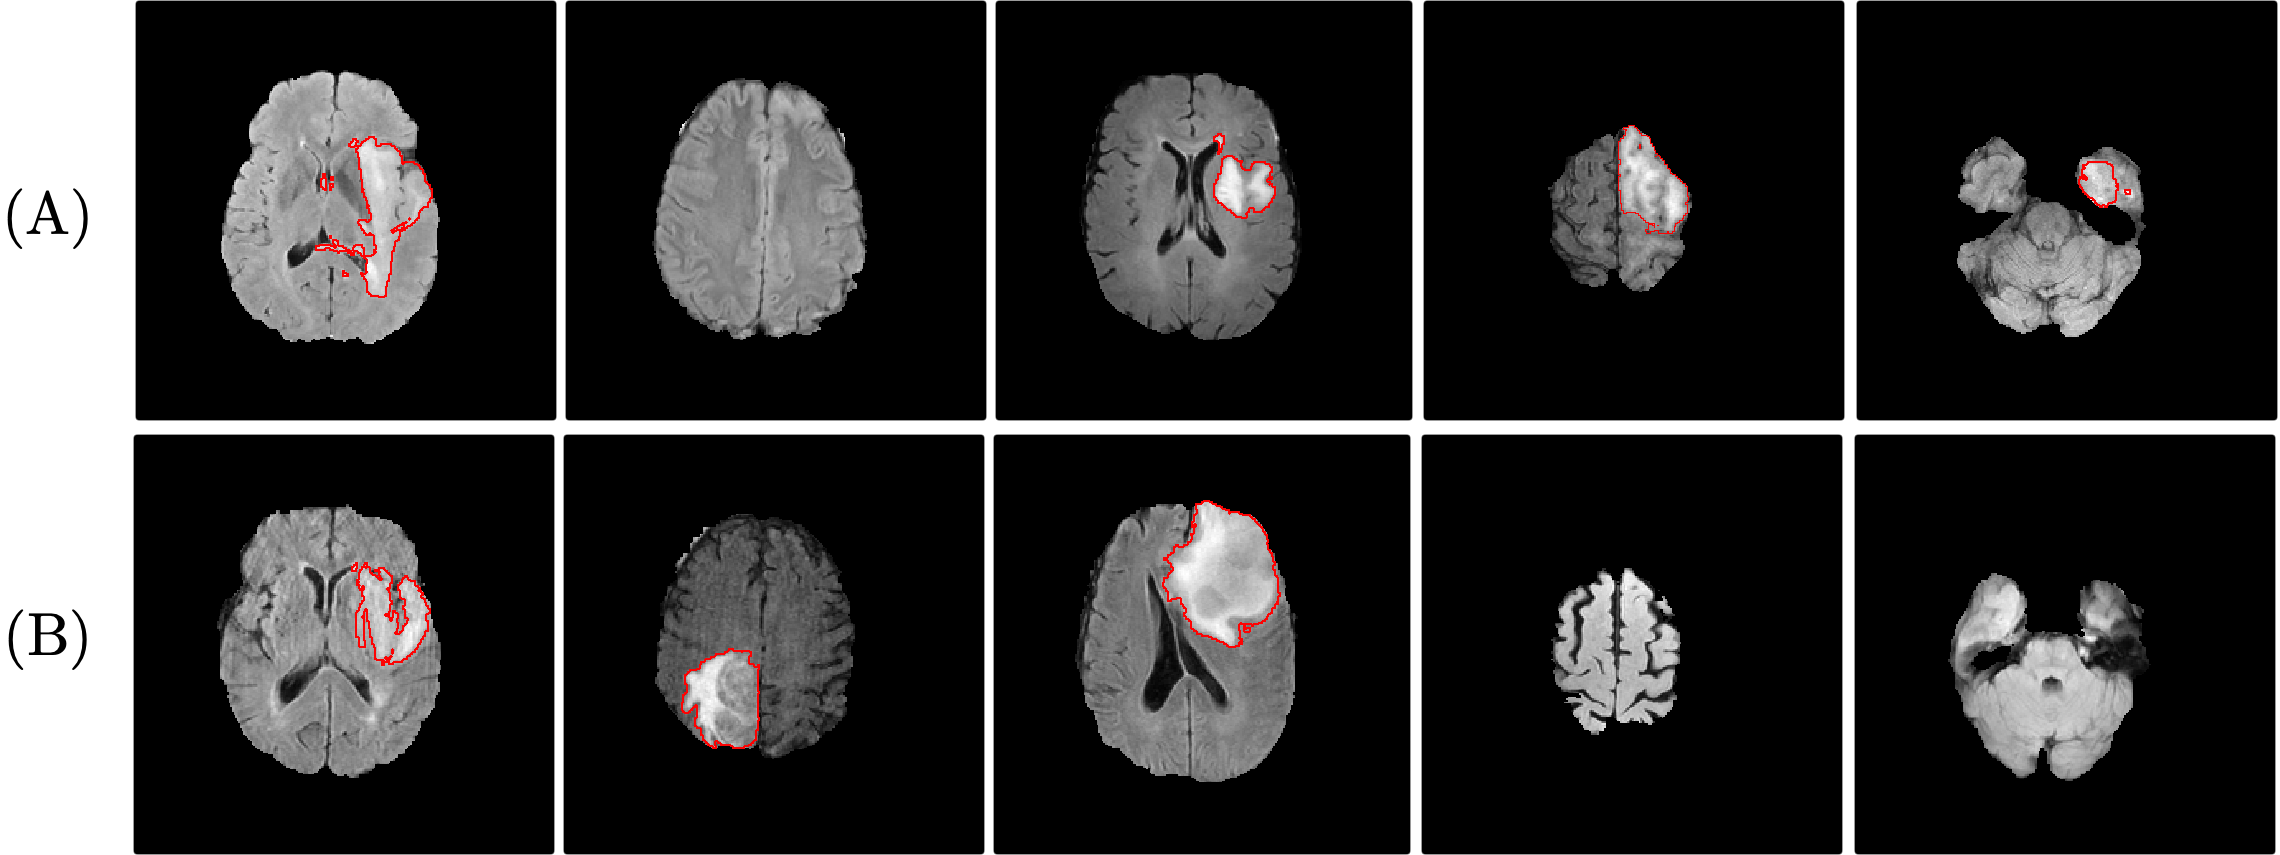

Fig. 3 compares the performance of the proposed method to the baseline random suggestion method and the oracle method, in terms of the Dice score for segmentation. It shows that when training from scratch (Fig. 3A), the proposed method outperforms the random suggestion under all circumstances. In addition, it yields similar or sometimes better performance compared to the oracle method. Training with 50 out of the full 260 volumes in BraTS dataset (19%) or 2,500 out of 39,000 image slices (7%) suggested by the proposed method achieved comparable performance to training on full dataset (a Dice score of 0.853 on full dataset is observed). For the transfer learning scenario (Fig. 3 (B)), the proposed method also consistently outperformed random suggestion and achieved comparable performance as the oracle method. Some examples of images suggested by proposed method for annotation are given in Fig. 4.

When we compare patient-wise suggestion to image-wise suggestion, the latter is better in annotation efficiency since much less images slices are suggested for annotation. In Fig. 3 (A), 2,500 images are suggested for annotation, which can achieve a similar performance as annotating 50 volumes (7,500 images). Even though some image slices are needed to provide the expert with the context in image-wise suggestion, given the expert would not need to annotate these context images, image-wise suggestion is still a more efficient method.